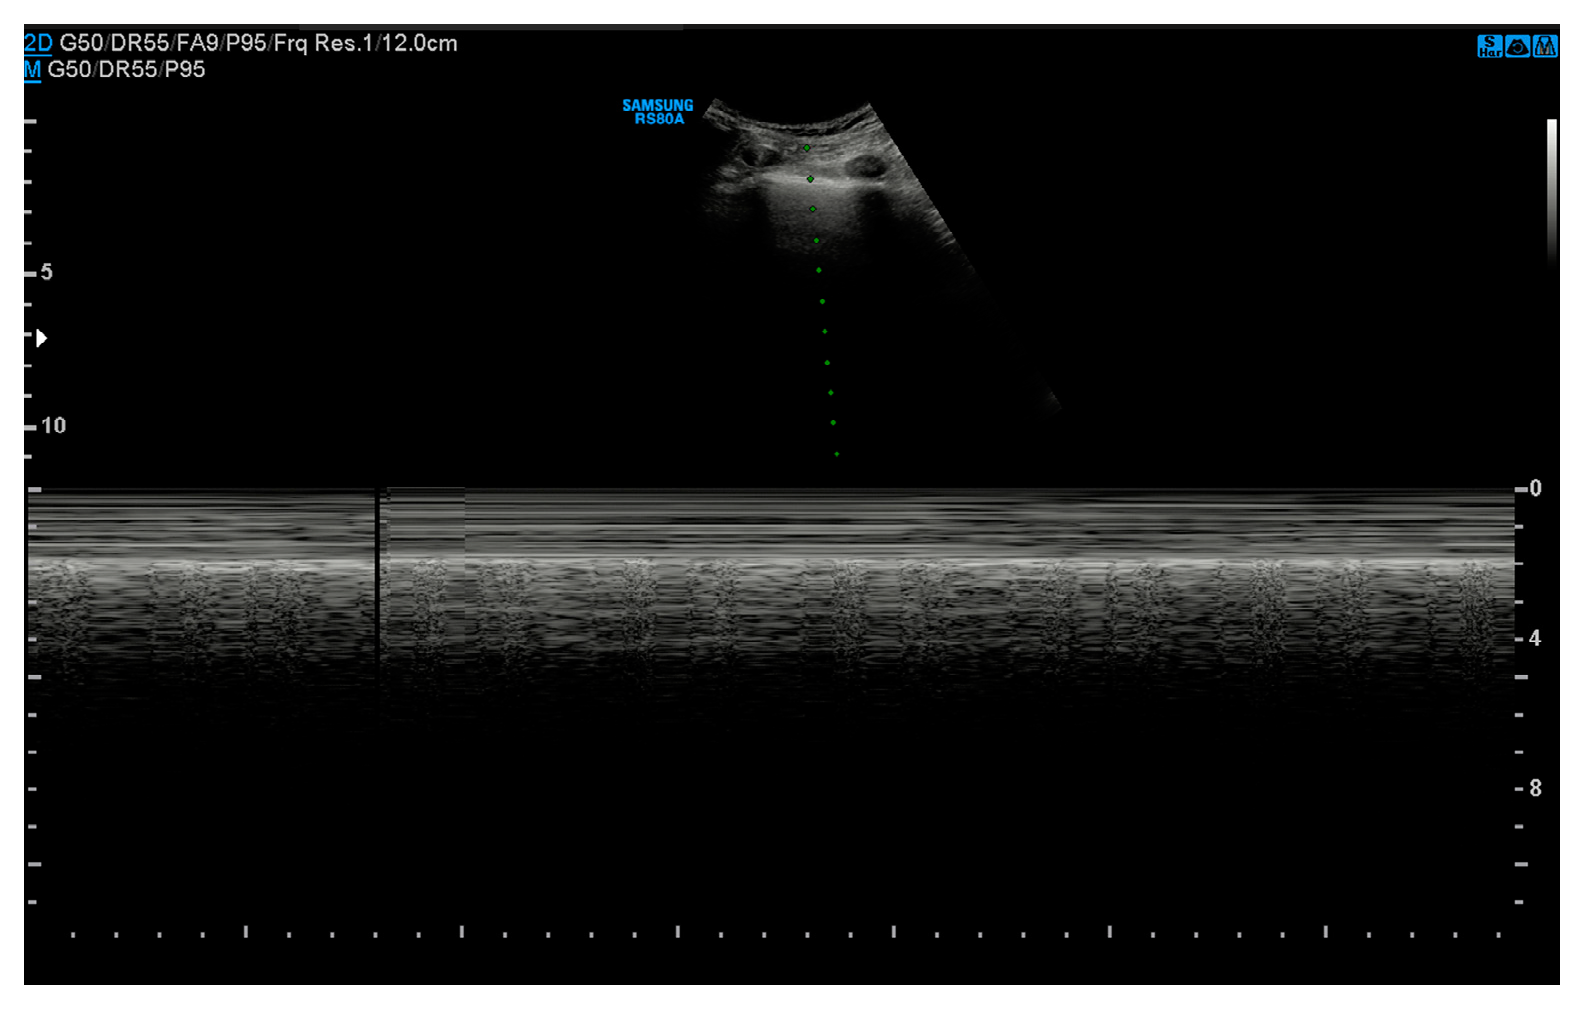

3.2. Ultrasound

- Absence of pleural sliding: Normally, the visceral pleura glides against the parietal pleura with respiration. In pneumothorax, this movement is absent;

- Absence of B-lines: Comet-tail artifacts (B-lines) are reverberation anomalies that disappear with the presence of air in the pleural space;

- Lung point sign: The point where normal lung sliding meets the absent sliding of the pneumothorax; this is highly specific for pneumothoraces;

- Barcode or stratosphere sign: A static, uniform appearance on M-mode ultrasound indicating loss of lung movement (Figure 3).